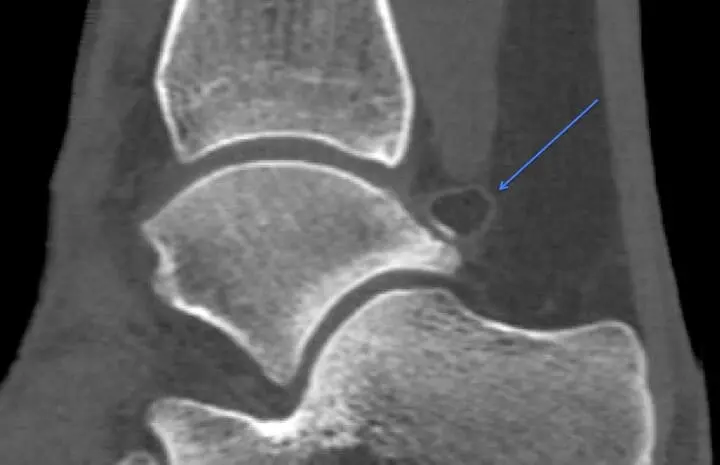

Des examens complémentaires, comme le scanner, restent indispensables à la recherche de lésions cartilagineuses, d’une arthrose débutante ou d’une souffrance ligamentaire,…